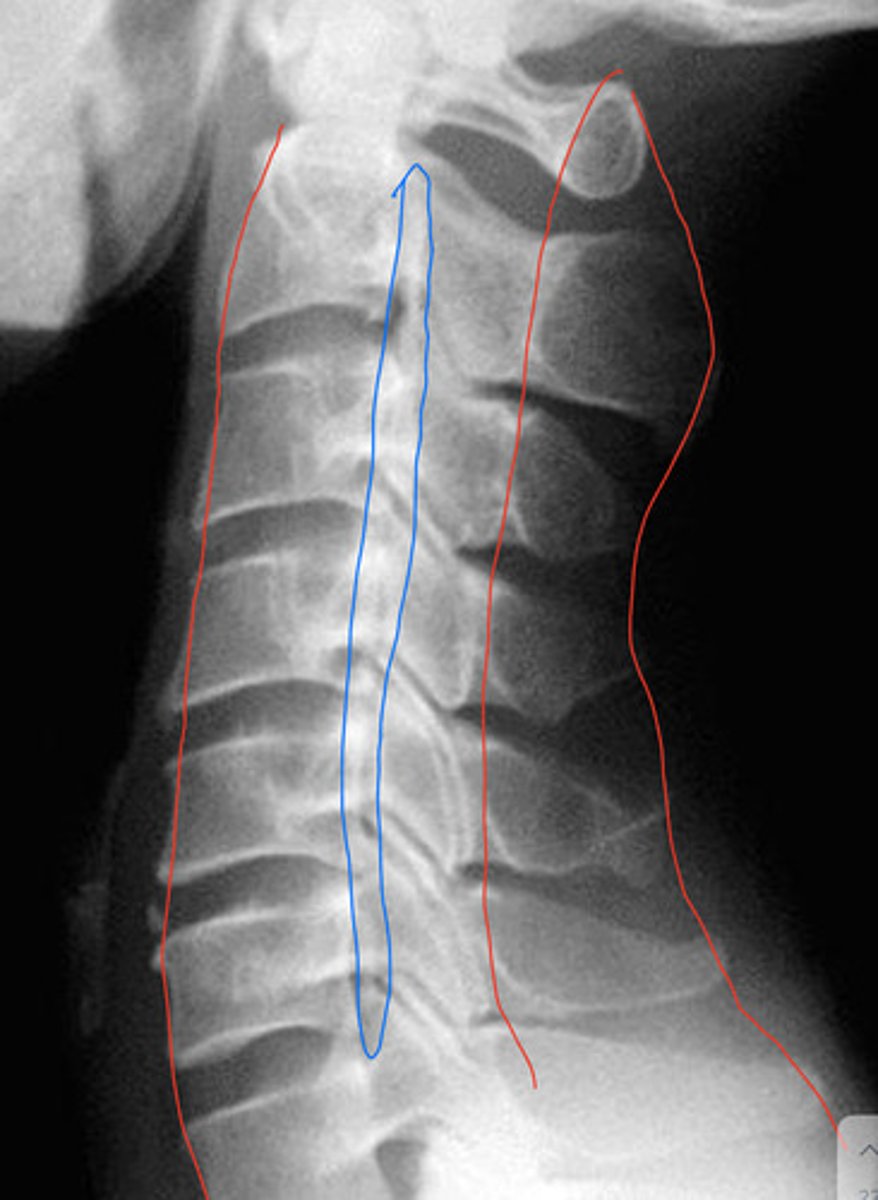

DISH

What is the blue arrow pointing at?

DISH (mid body to mid body)

What is the arrow pointing at?

DISH (mid body flow of the anterior vertebral line)

What is wrong with this image?

Calcification of ALL or DISH

What is the pathology?